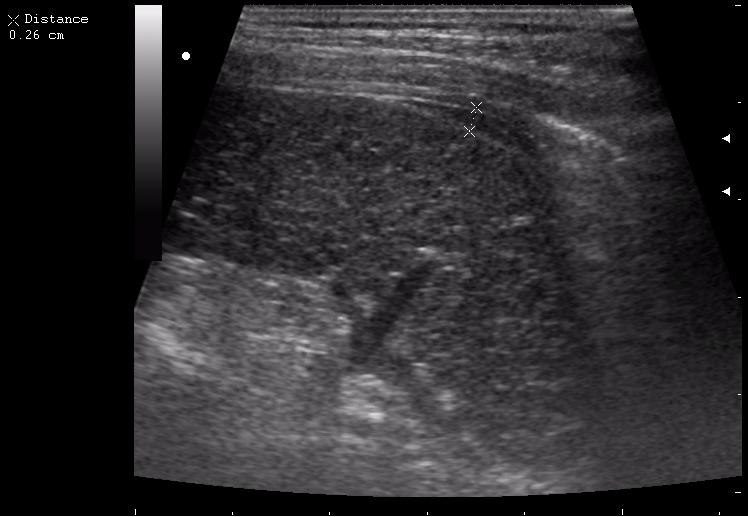

наезд большой черной Прады на маленькую (13кг) 5-летнюю девочку.

получает Медаксон, рабочая версия - изменение желчного пузыря вследствии травмы (шепотом - рекомендация хирургу сменить антибиотик)